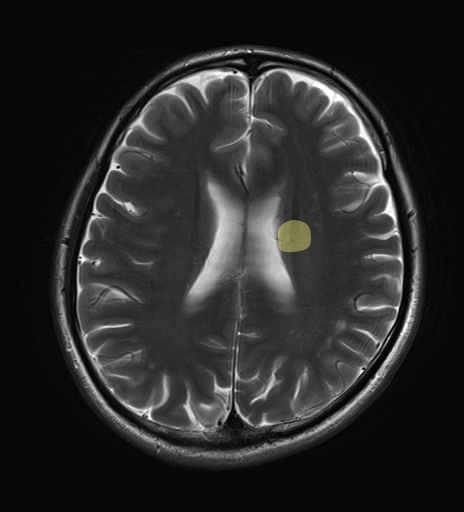

運動系 錐体路系に色を付けました。

■皮質脊髄路(いわゆる錐体路):一次運動野から脊髄遠隔の下位運動ニューロン細胞体まで